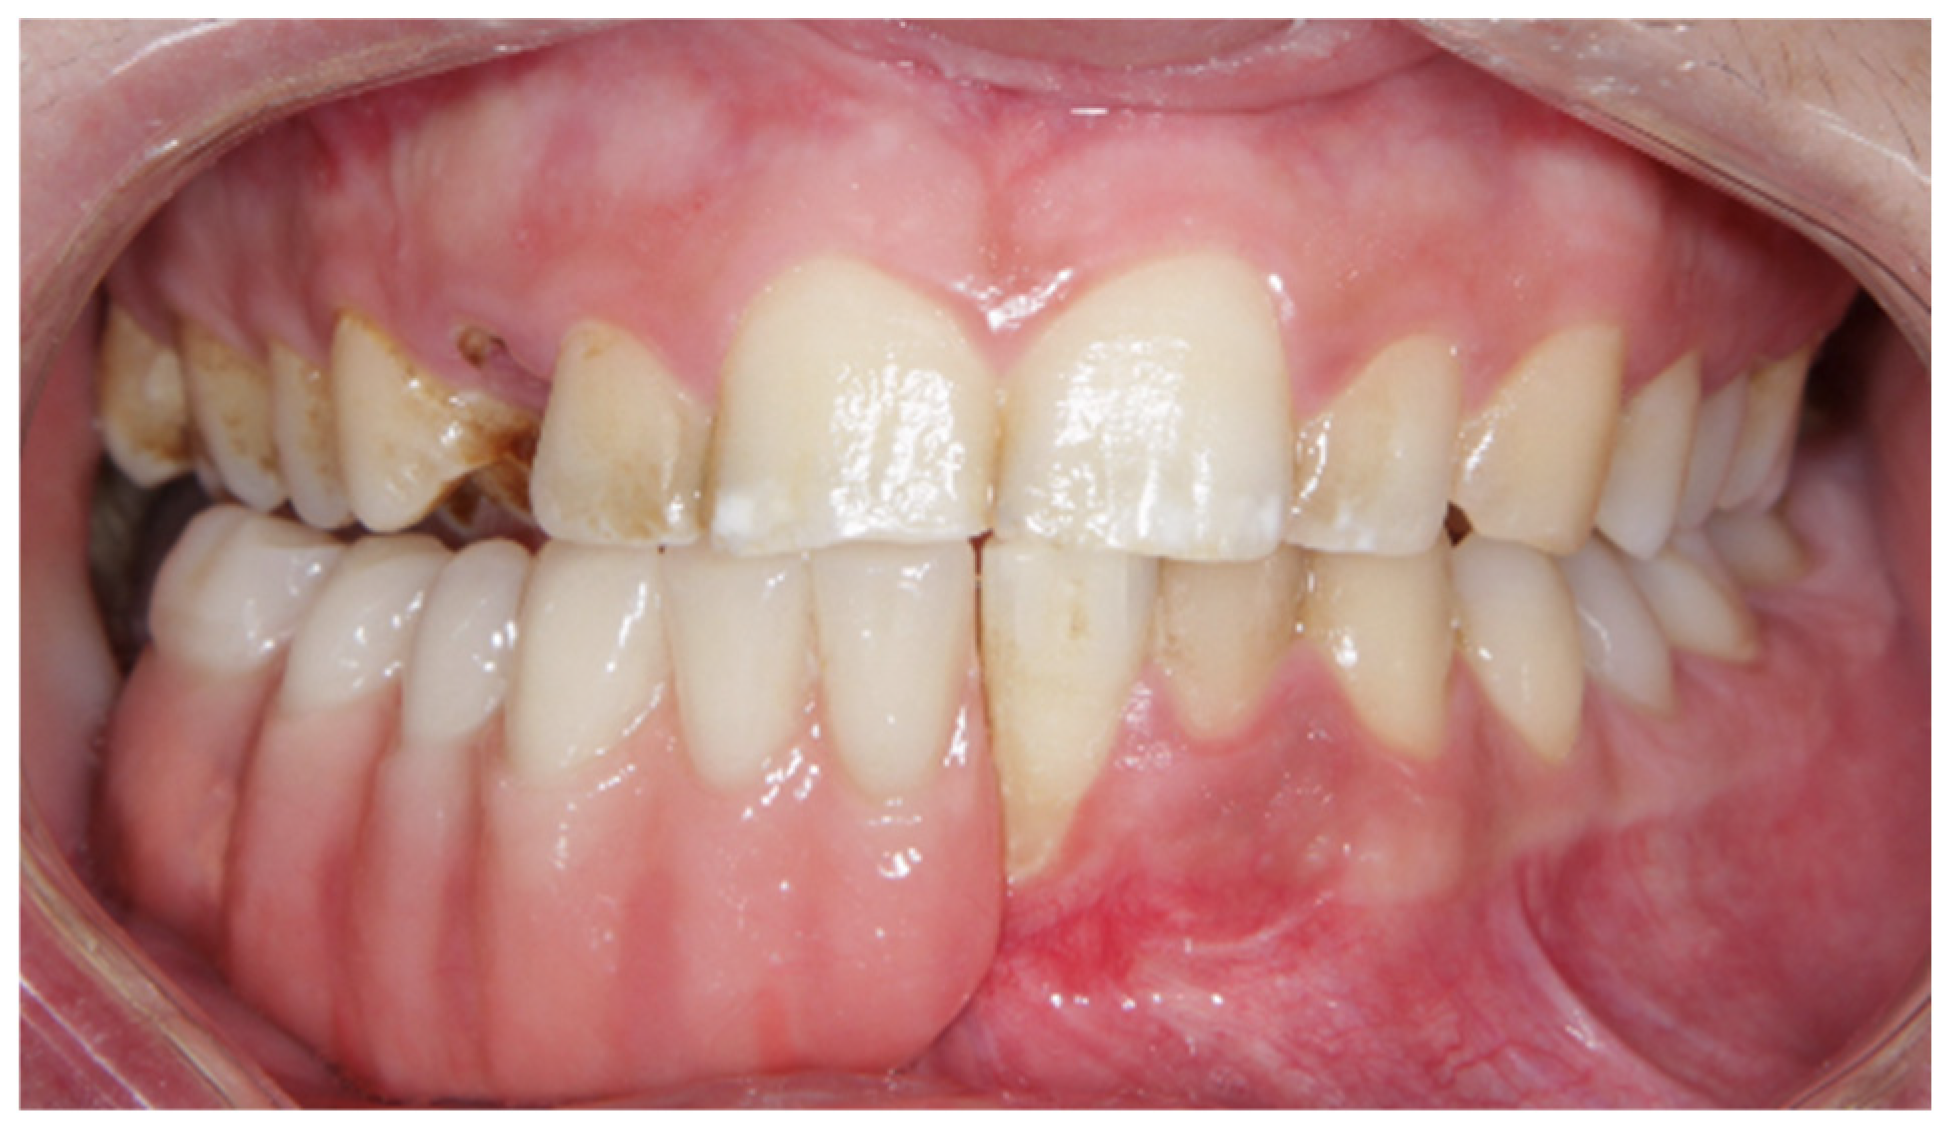

2. Materials and Methods

Clinical Case

| 2022 | Periodontal control |

| 2022–2023 | Complementary exams and planification |